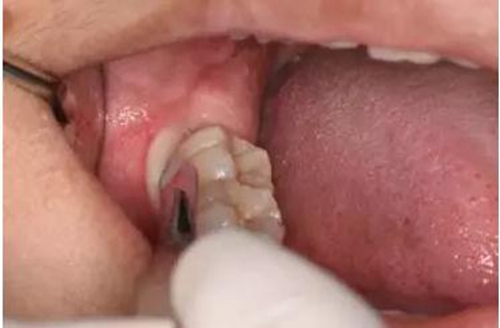

圖9.翻小瓣、用骨膜剝離器輕柔牽拉頰側(cè)齦瓣、暴露48合面

圖10.普通牙挺放置在48牙冠的近中根面與牙槽嵴頂之間,采用推力和挺力,挺松48.

圖11.以頰側(cè)骨板做支點(diǎn)、往上脫位